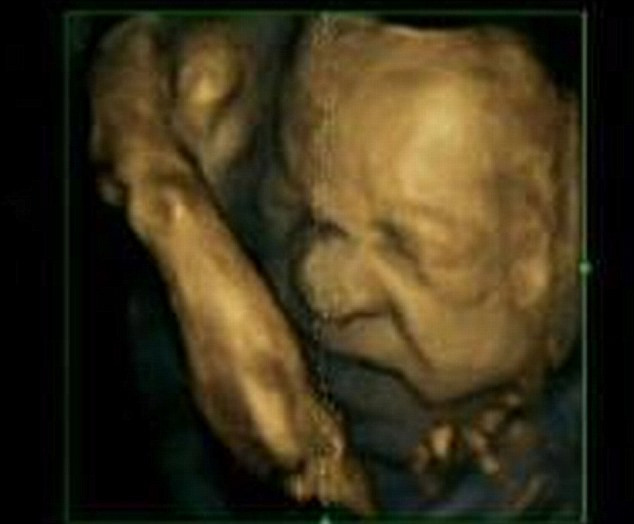

In ecografii sunt surprinse in cele mai mici detalii gesturile fetei pe care copiii din pantece le fac.

Imaginile au fost realizate cu ajutorul unui ecograf 4D care reuseste sa surprinda copilul in pantece in cel mai marunt detaliu posibil.